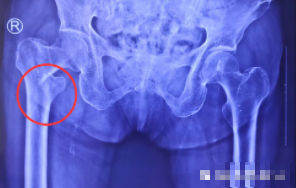

术前

来到我院后,关节外科医生为张奶奶进行了仔细检查,通过X线片显示,张奶奶右股骨粗隆间骨折。